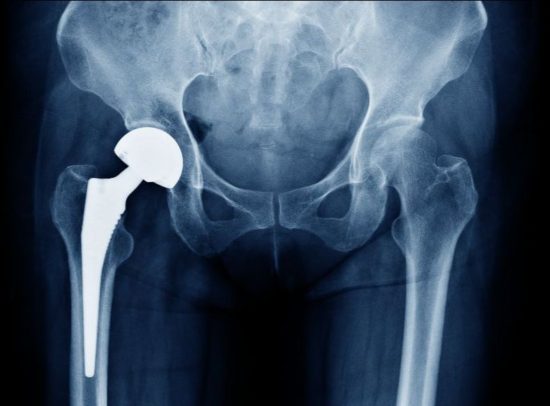

A new publication by Dartmouth College researchers on the New Hampshire NSF EPSCoR Track 1 project, NH BioMade, reviews the addition of nanoparticles in various stages of joint arthroplasty surgery. Since these surgeries, specifically total knee arthroplasty (TKA) and total hip arthroplasty (THA) are increasingly common in younger patients, making these joint implants more durable is critical to improving patient outcomes.